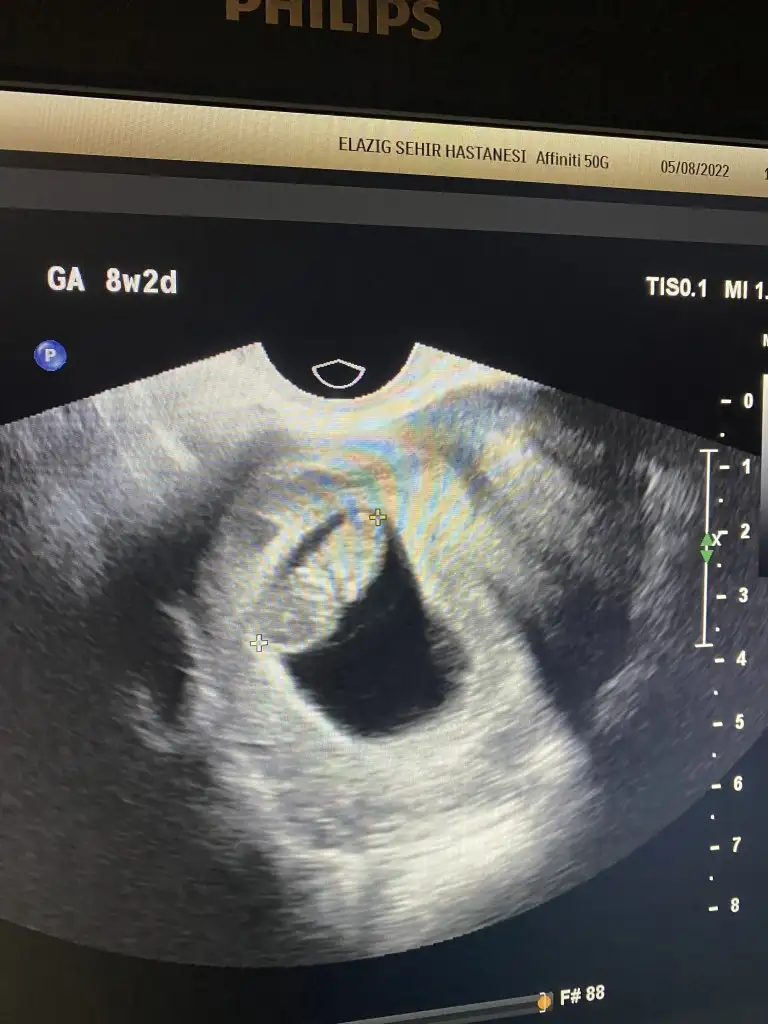

4-8-12 haftalık ultrason görüntüleri bebeğimin hepsi karından cinsiyetini tahmin eder misiniz acaba

Merhaba 9+3 karından